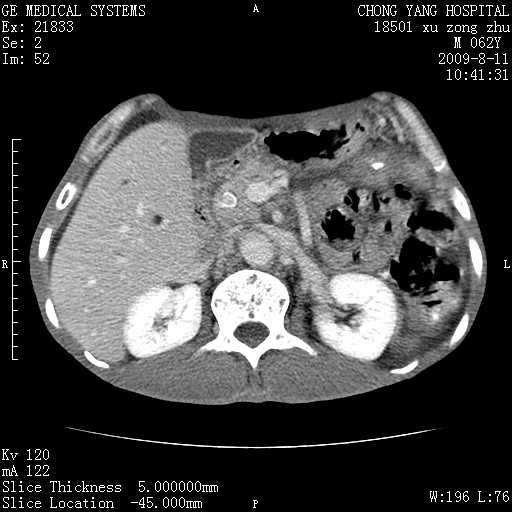

以下是引用杀毒软件在2009-8-11 16:35:00的发言:[br]肝内胆管扩张局限于左叶,胆管内有结石伴肝外胆管结石,胆管壁增厚呈弥漫性并发腹腔积液,胰腺边界模糊。[br][br]考虑---胆总管及肝内胆管结石继发胆管炎及胰腺炎,左肾下极囊肿,腹水。

以下是引用zjzjr在2009-8-11 17:35:00的发言:[br]肝内胆管扩张局限于左叶,胆管内有结石伴肝外胆管结石,胆管壁增厚呈弥漫性并发腹腔积液。[br][br]考虑---胆总管及肝内胆管结石继发胆管炎,左肾下极囊肿,腹水。